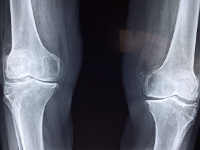

셋째, 정기적인 검진을 받으십시오. 무릎 관절의 문제는 초기에 발견하면 치료가 쉽고 효과적입니다. 반면에 문제가 심해지면 수술이나 장애 등의 심각한 결과를 초래할 수 있습니다. 따라서 무릎 관절에 이상이 있거나 통증이 지속되면 의사에게 상담하고 검진을 받으십시오. 의사는 적절한 진단과 치료 방법을 제시해줄 것입니다. 또한 정기적으로 X-선이나 MRI 등의 검사를 통해 무릎 관절의 상태를 확인하고 예방할 수 있습니다.